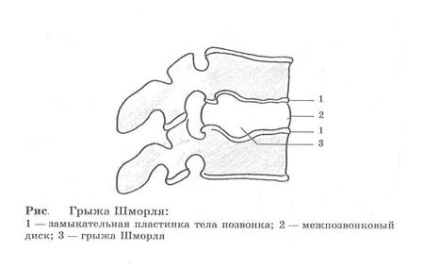

Acest lucru, încă o dată, - semne radiologice care indică modificări în structura discului intervertebral și corpul vertebral.

Această proeminență cartilaj special garnitură de corpul vertebral, corpul de mai sus sau vertebre care stau la baza.

Thin numit endplates cartilaj hialin, el este în partea de sus și de jos a discului intervertebral.

După o astfel de deformare în corpul vertebral acoperit deasupra sau sub cartilajul hialin menționat mai sus, este introdus nucleul pulpos al discului intervertebral.

Astfel, un cartilaj proeminență apex în formă de pană confruntă deteriorate interior vertebră, baza care „minciuni“ în discul intervertebral.

Conform modelului cu raze X SHmorlja hernie poate fi descrisă în diverse moduri, să ne ia în considerare pe scurt fiecare dintre tipurile de semne radiologice.